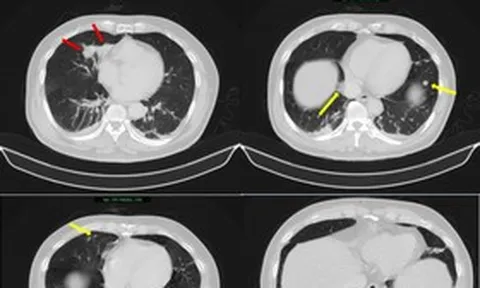

(NLĐO) - Từ một nốt mụn bọc ở vùng mông, nam sinh rơi vào tình trạng sốc nhiễm khuẩn, suy đa tạng, hai phổi đầy ổ áp xe, tổn thương hoại tử lan rộng.

Ca robot mổ điều trị phổi biệt lập đầu tiên tại Việt Nam

Ngày 2-3, Bệnh viện Bình Dân (TP HCM) cho biết vừa thực hiện thành công ca phẫu thuật robot cắt thùy dưới phổi trái điều trị bệnh lý phổi biệt lập nội thùy.